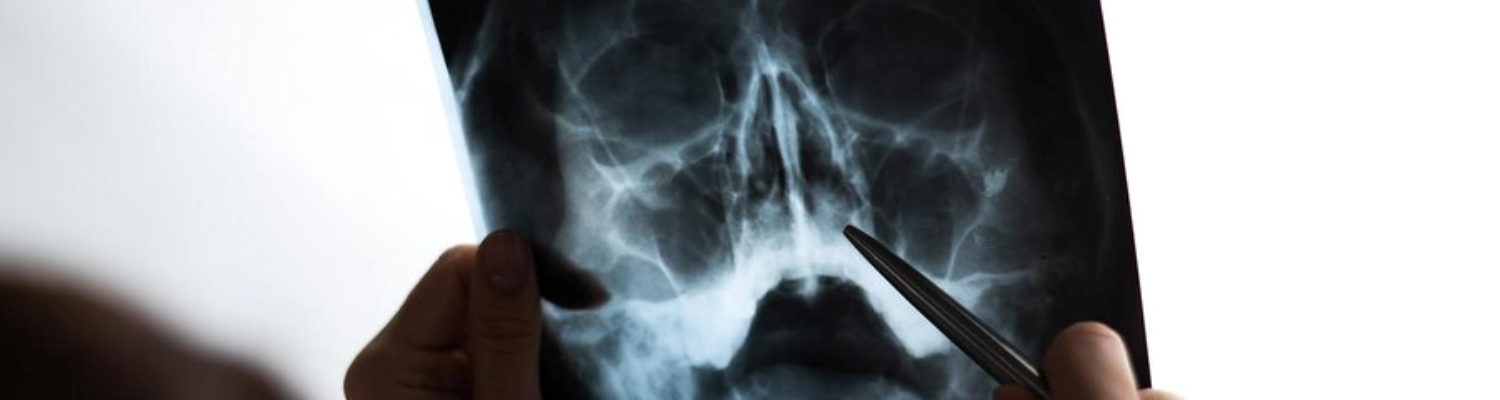

Рентгенографія придаткових пазух носа у МЦ "Healthy&Happy" в Києві

Рентгенографія придаткових пазух носа — це один із найбільш інформативних методів діагностики, який дозволяє виявити запальні процеси, аномалії розвитку та новоутворення у носових пазухах. Дослідження допомагає своєчасно поставити діагноз і розробити ефективний план лікування.

- Процес: Лікар-радіолог робить знімки у кількох проєкціях (пряма та бічна), що дозволяє оцінити стан гайморових, лобних і решітчастих пазух.